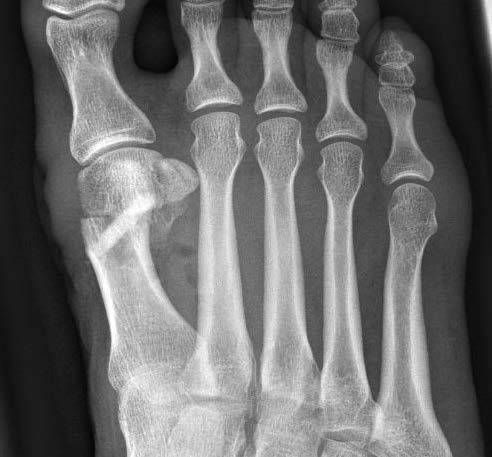

Röntgenbild postoperativ, schräg

Liegendes Shark Screw® Transplantat erkennbar. Korrektur durch subcapitale Metatarsalosteotomie nach Austin.